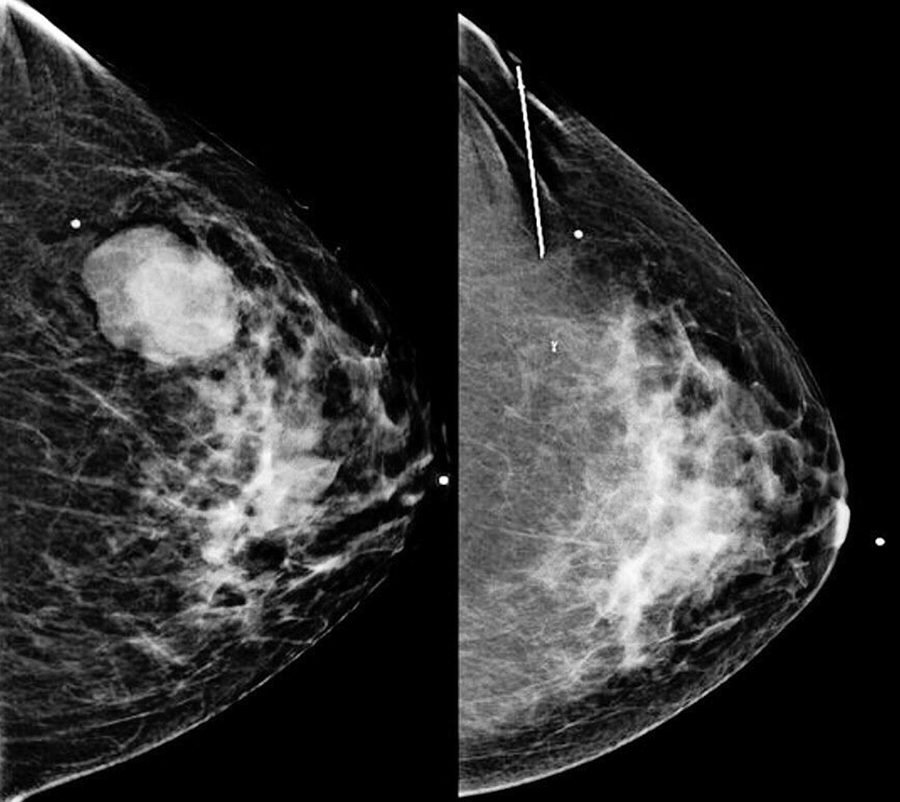

Cáncer de mama triple negativo